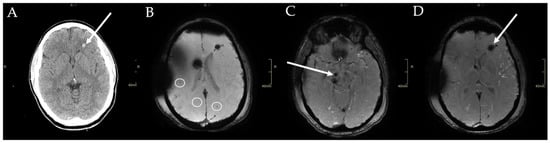

2.1. Patient Information